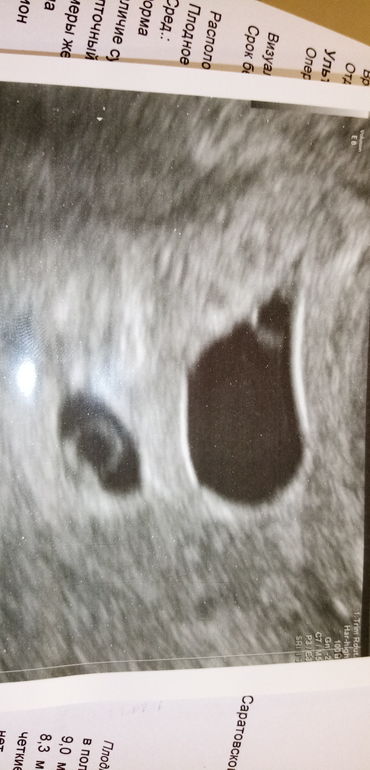

Ди-Ди двойня

Многоплодная беременностьКрио в ЕЦ два эмбриона. Сейчас с УЗИ